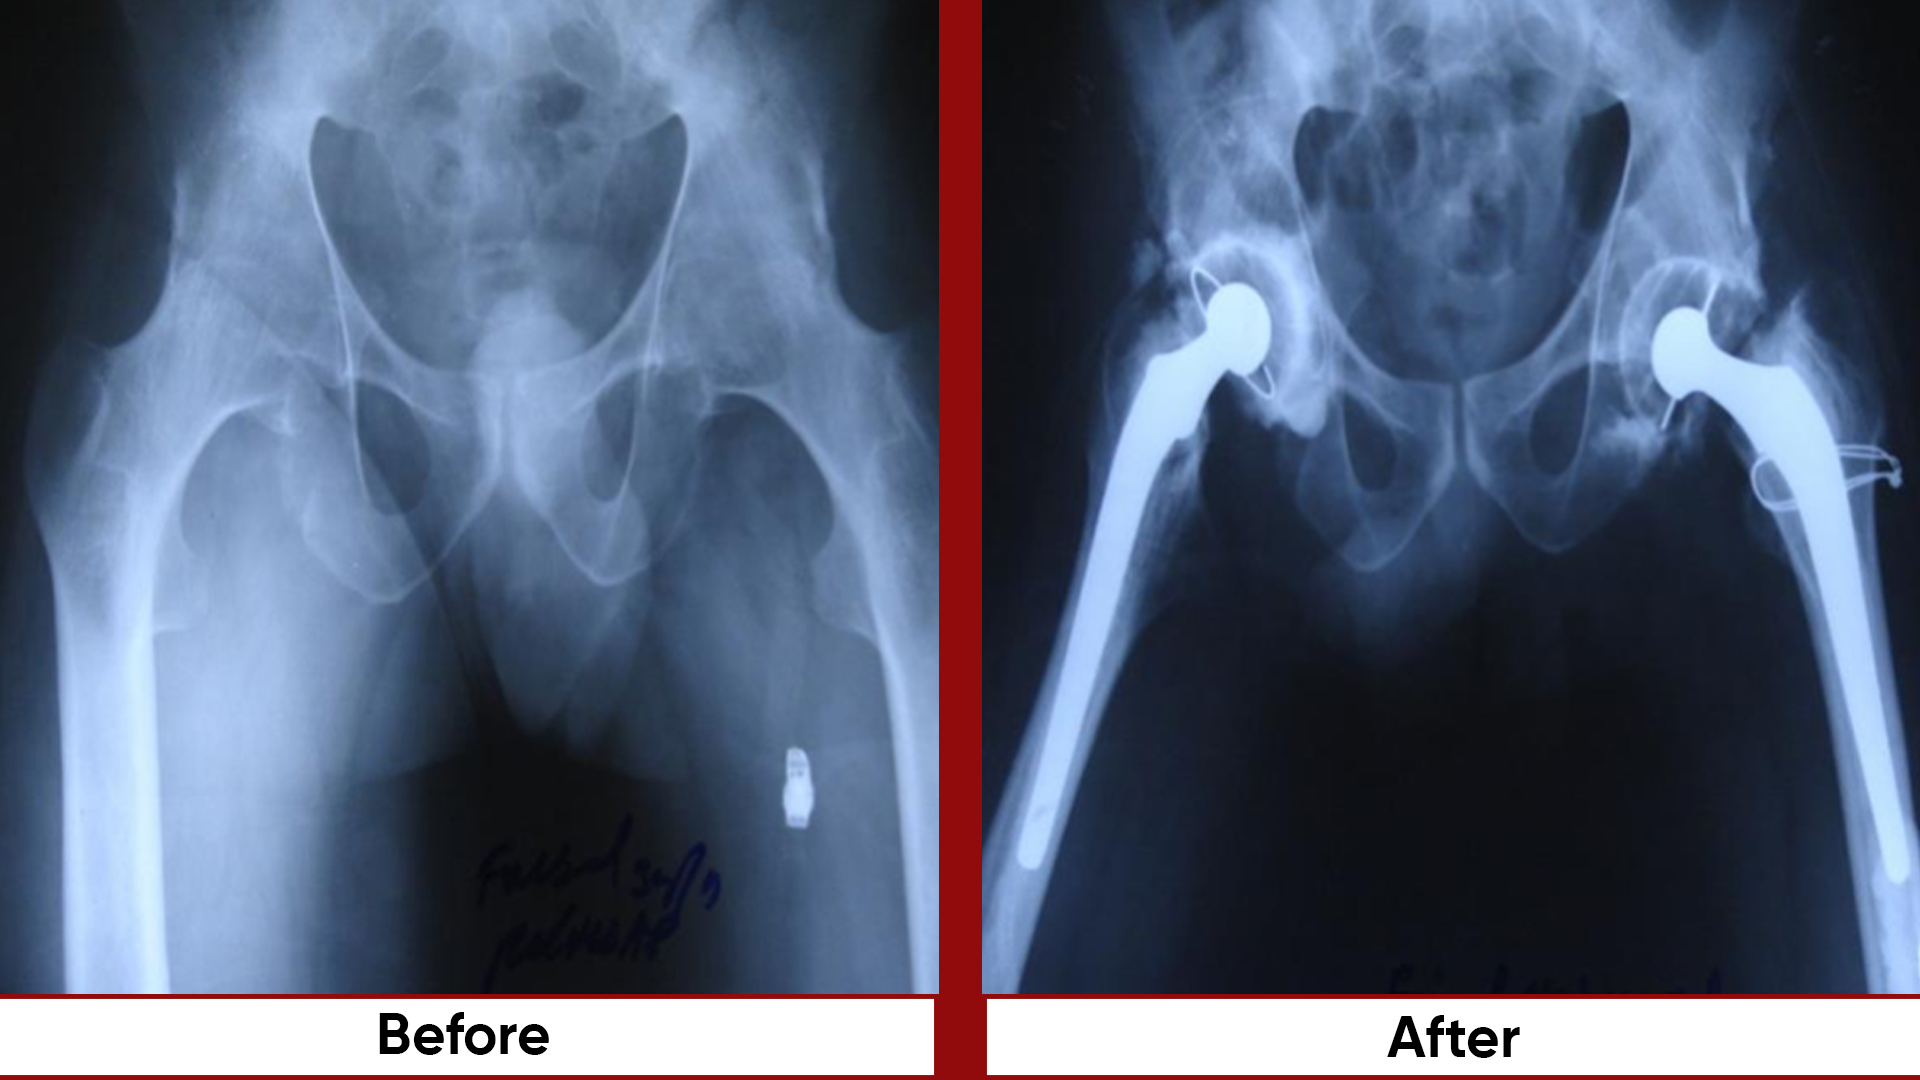

• Total Hip Replacement (THR)

• Arthroplasty